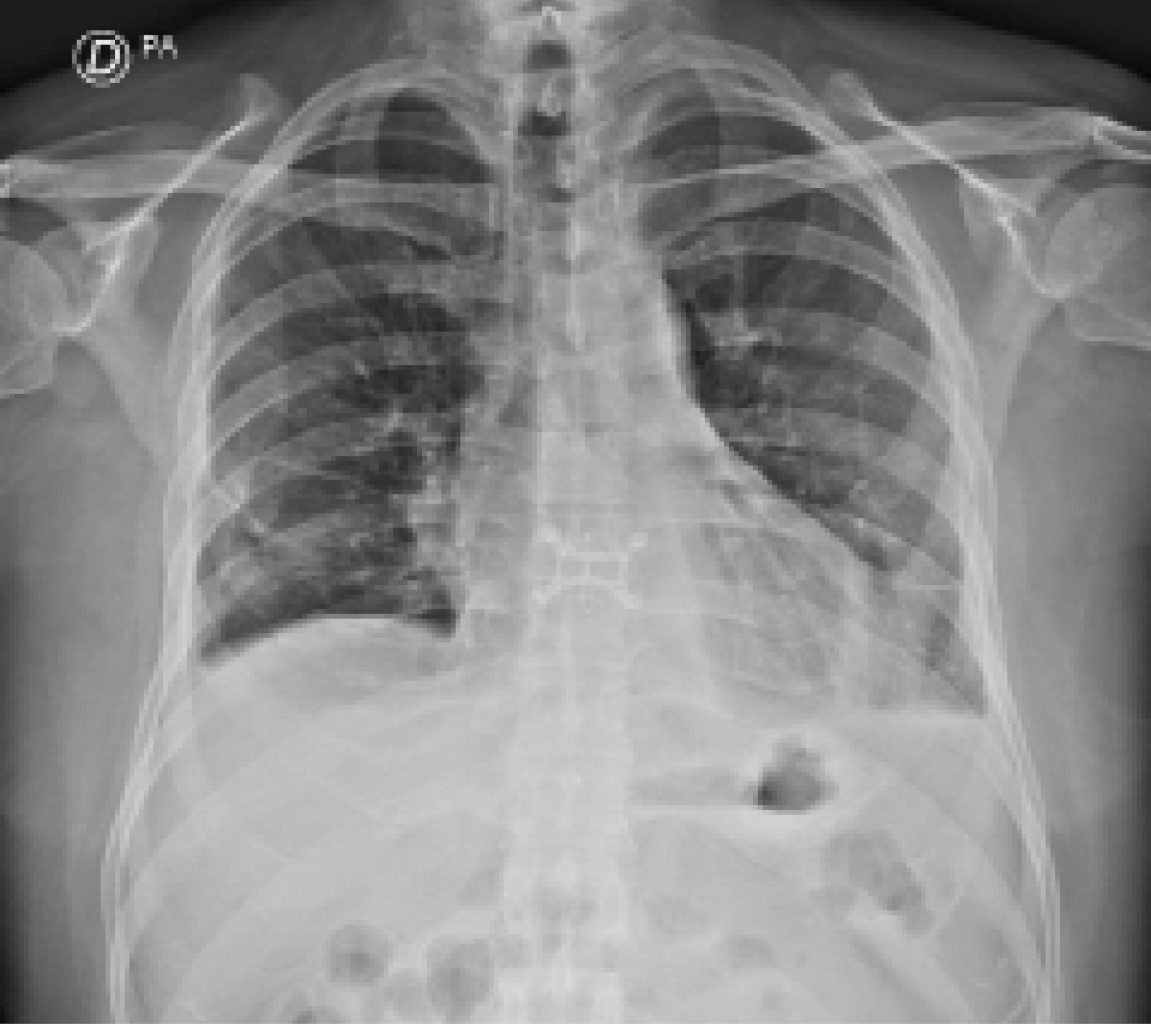

De los pacientes que aquí reportamos, queremos resaltar al paciente de 55 años de edad que fue sometido a trasplante bipulmonar. Su evolución clínica dibuja una imagen que sin duda veremos replicarse globalmente en todos los programas de trasplante. Es aquel paciente afectado por secuelas pulmonares severas por SARS-CoV-2 (Figura 1), que sobrevive generalmente conectado a algún tipo de soporte vital extracorpóreo y que acorde a lo reportado en la literatura,12 cumpliría con los requisitos para ser candidato a trasplante en esta condición.

Figura 1